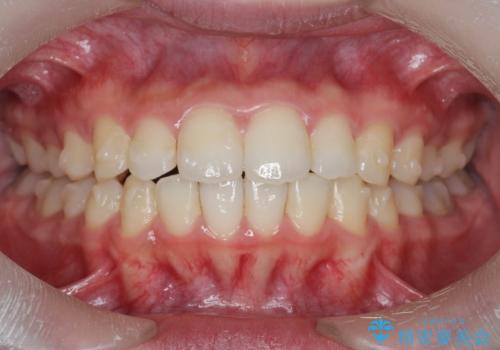

出っ歯を治すマウスピース矯正

- 出っ歯のように見える前歯の角度を治したい、と矯正治療を希望され来院されました。

抜歯をせずにマウスピース矯正システムインビザラインを用いてしっかりと前歯の角度を改善していきます。

前歯の角度だけでなく内側に倒れ込んでいた奥歯もしっかり起こすことで咬合関係も理想的に仕上げています。